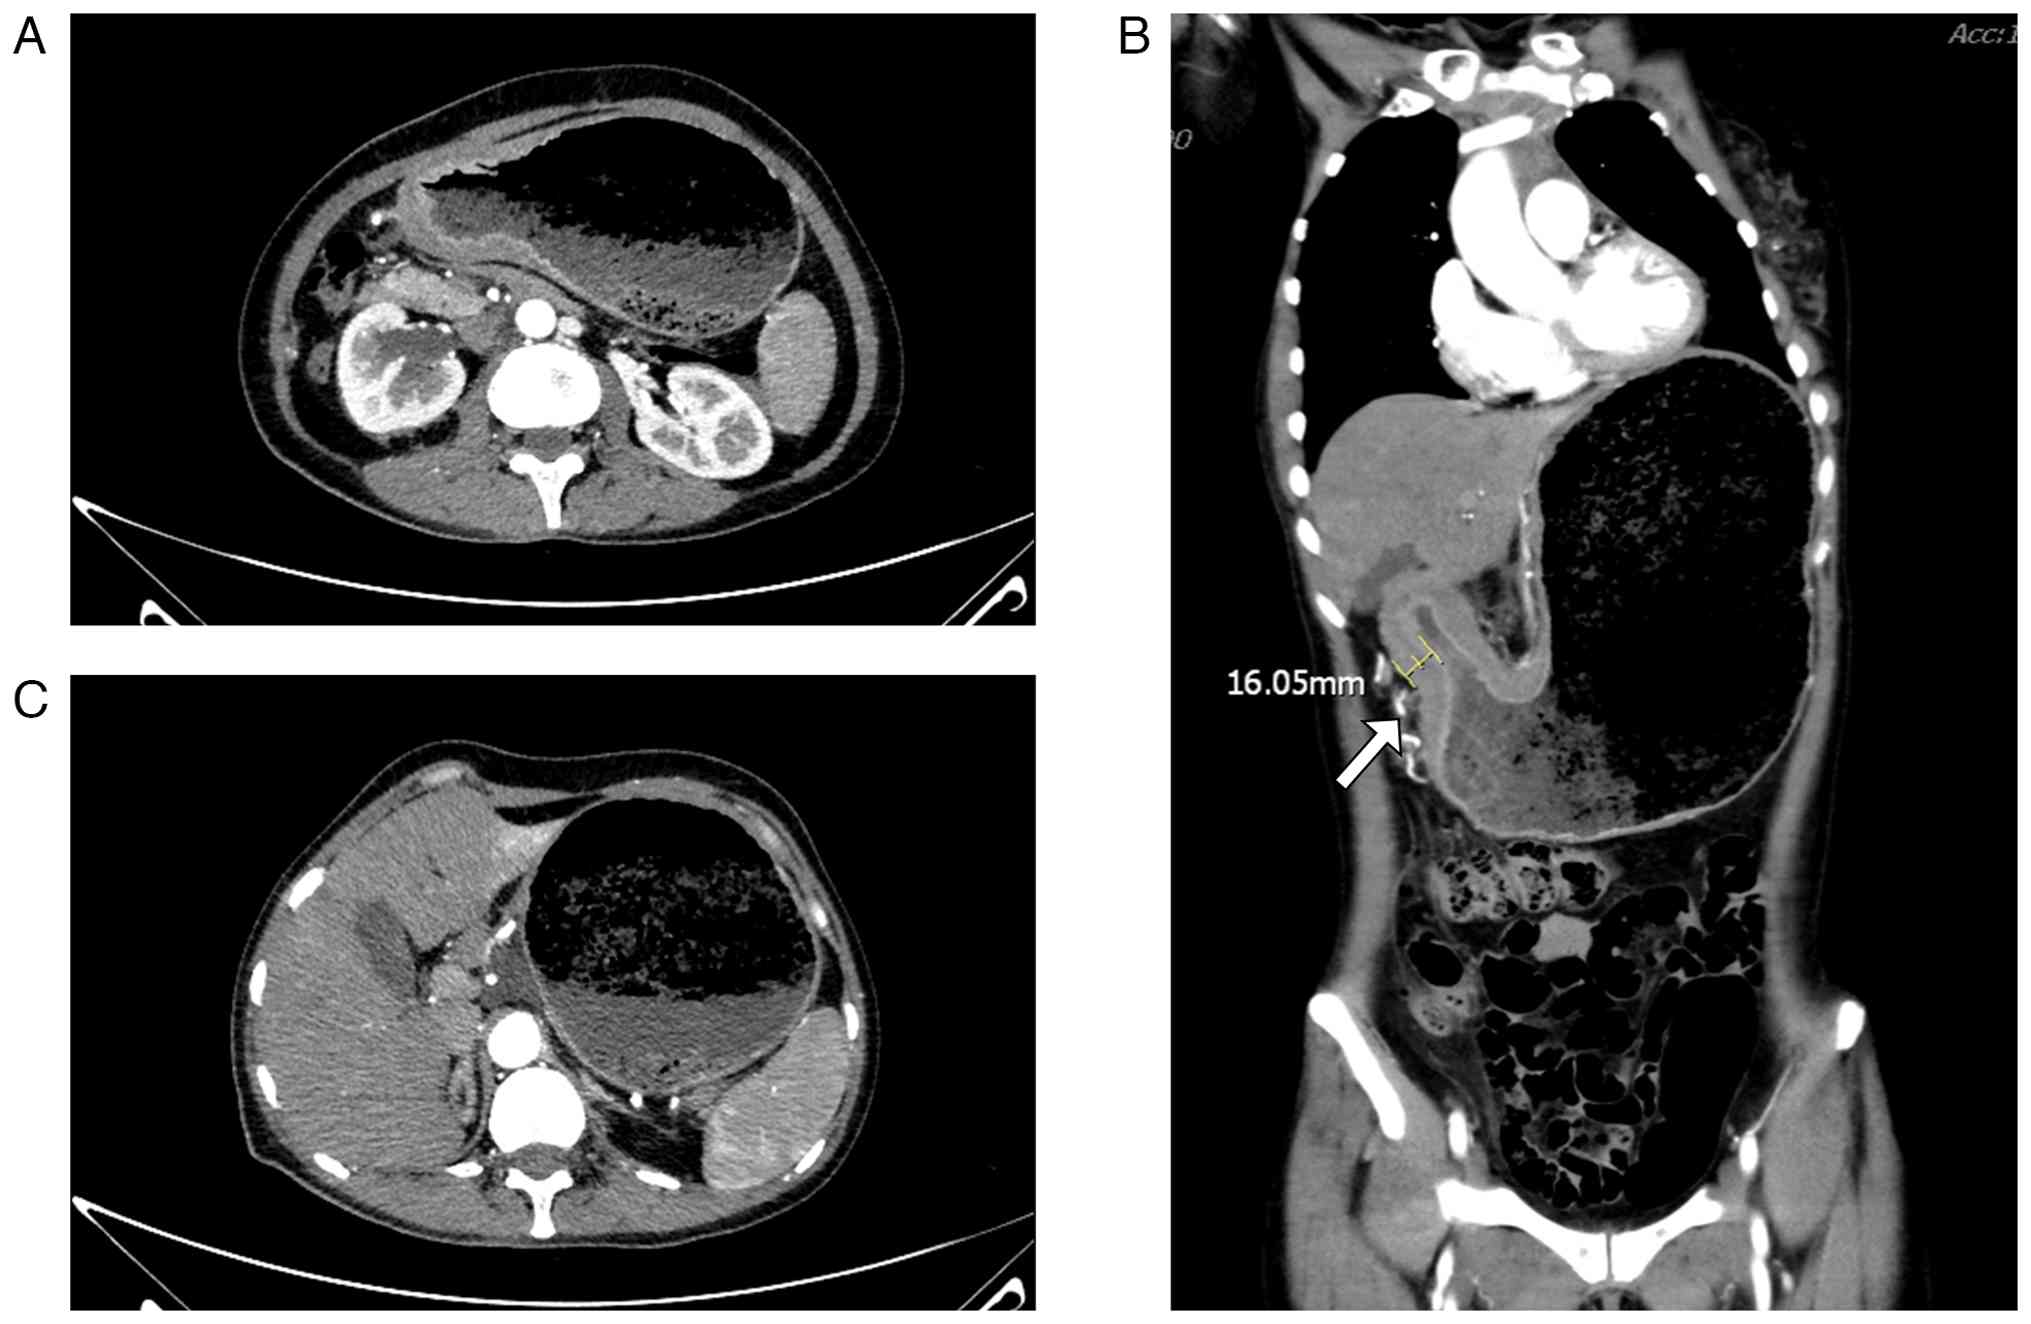

A total of 1 month later (36 days after the last conducted CT), in February 2022, the patient was readmitted due to persistent abdominal distension. Follow-up contrast-enhanced CT performed in February 2022 revealed progressive diffuse and irregular gastric wall thickening (maximum thickness 19.04 mm; Fig. 4C) extending from the fundus and body to the pyloric region, exhibiting heterogeneous enhancement and focal luminal narrowing (Fig. 4A-C). Additionally, newly enlarged nodules were detected within the hepatogastric ligament (Fig. 4B). The mesentery, omentum and peritoneal surfaces exhibited thickening, stranding and nodular changes, with newly identified implant-like nodules (Fig. S5). These findings were highly suggestive of metastatic disease. The persistent and progressive symptoms, coupled with the new radiographic evidence of peritoneal disease and the ongoing disparity between profound functional gastric outlet obstruction and the lack of a fixed luminal lesion, strengthened the suspicion of a motility disorder secondary to metastatic infiltration. Endoscopic ultrasound (EUS) and gallium-68 fibroblast activation protein inhibitor positron emission tomography/CT (68Ga-FAPI PET/CT) were considered but not performed owing to concerns regarding the tolerance and safety of the patient

Follow-up contrast-enhanced CT

imaging revealing disease progression. (A) Axial CT image shows

diffuse and irregular gastric wall thickening with heterogeneous

enhancement. (B) Coronal CT image demonstrates progressive, diffuse

and irregular wall thickening extending from the gastric

fundus/body to the pyloric region, with heterogeneous enhancement.

(C) Axial CT image reveals a newly enlarged nodule within the

hepatogastric ligament, highly suggestive of metastatic

involvement.

Figure 4

Follow-up contrast-enhanced CT imaging revealing disease progression. (A) Axial CT image shows diffuse and irregular gastric wall thickening with heterogeneous enhancement. (B) Coronal CT image demonstrates progressive, diffuse and irregular wall thickening extending from the gastric fundus/body to the pyloric region, with heterogeneous enhancement. (C) Axial CT image reveals a newly enlarged nodule within the hepatogastric ligament, highly suggestive of metastatic involvement.